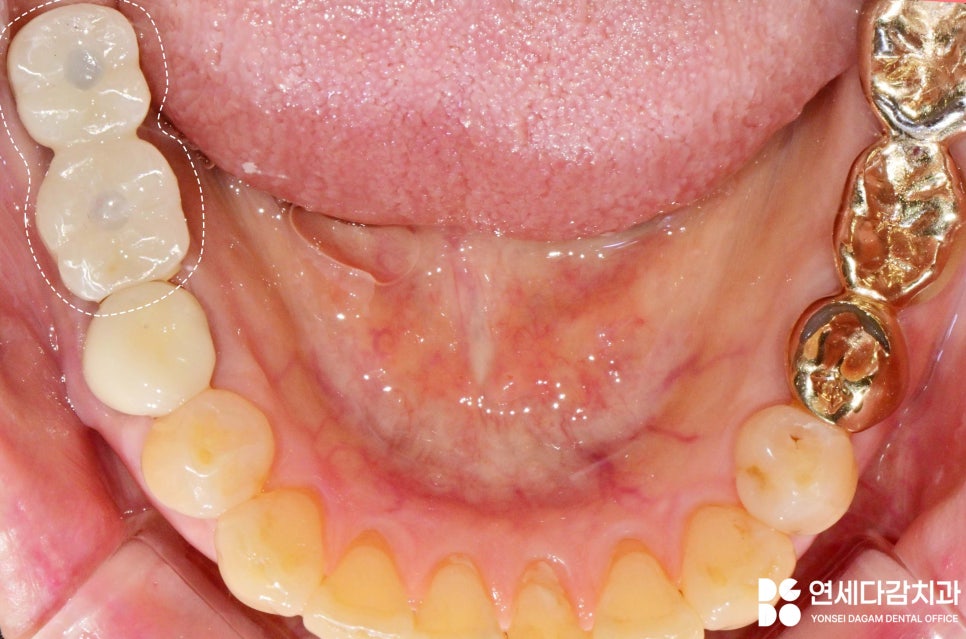

오래된 보철의 큰 특징은

치아 사이 긴밀함이 떨어져

음식물이 이 사이에 많이 끼고,

저작기능이 떨어진다는 점입니다.

문정동 치과 에서

15년 이상 된 보철을 살펴보면

많이 닳고 깨진 모습을

볼 수 있습니다.

오래된 보철물의 screw를 빼고 보니

문정동 치과 에서 육안으로 보기에

external octa fixture라고 생각했습니다.

(8각형 모양의 연결 부위가

외부로 돌출되어 있는 타입)

그러나 겉모습만으로는 정확한

구조를 파악하기는 어렵기 때문에

이런 상황에서는 치근단 엑스레이를

찍어서 임플란트의 내부 구조를

정확히 확인합니다.

확인 결과 스크류가 하나 더 있는 것을

알 수 있었습니다.